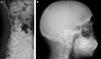

En los últimos 6 meses, 17 personas con enfermedad renal crónica (ERC) terminal en situación de hemodiálisis (HD) han acudido al Servicio de Urgencias del Hospital 12 Octubre para continuar con sus sesiones habituales. El número de las personas que han llegado no ha dejado de aumentar en los últimos años (fig. 1). Cada una de estas personas nos recuerda que la humanidad y la globalización están fallando, y que existe un abismo en la equidad al acceso al TRS entre países. Y, por otro lado, nos están enseñando los signos clínicos clásicos de la enfermedad renal, que los nefrólogos occidentales habíamos olvidado porque son el fruto de la infradiálisis mantenida (fig. 2). Estas personas, después de endeudarse para pagar el tratamiento en los países donde la cobertura sanitaria no los protege, escapan de su realidad para seguir viviendo. Algunos de ellos, con suerte tienen familia o amigos que los acogen, otros vienen solos, y se acaban encontrando en situación de calle. Los migrantes en TRS carecen de permiso de residencia, y de permiso de trabajo. Además de presentar las dificultades laborales del enfermo terminal, que precisa atención hospitalaria 3 veces a la semana.